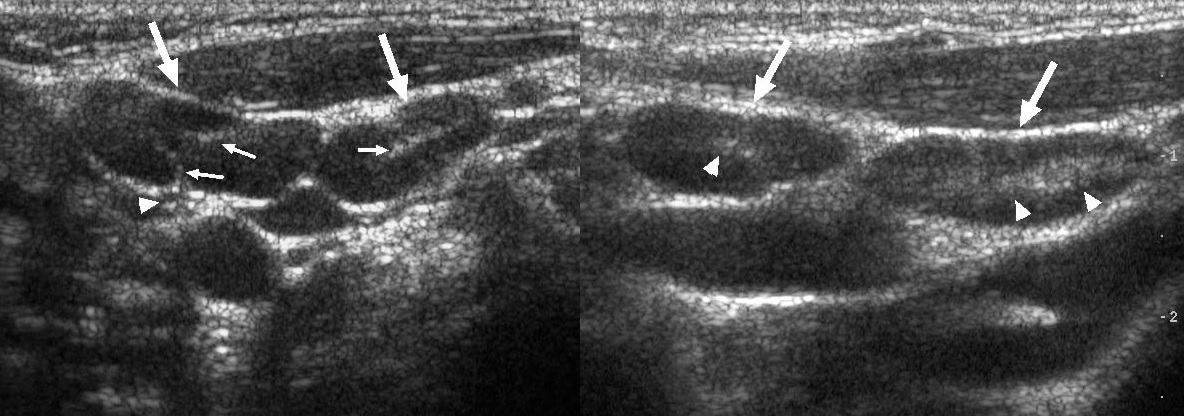

Мезентериальные лимфатические узлы: УЗИ и диагностика